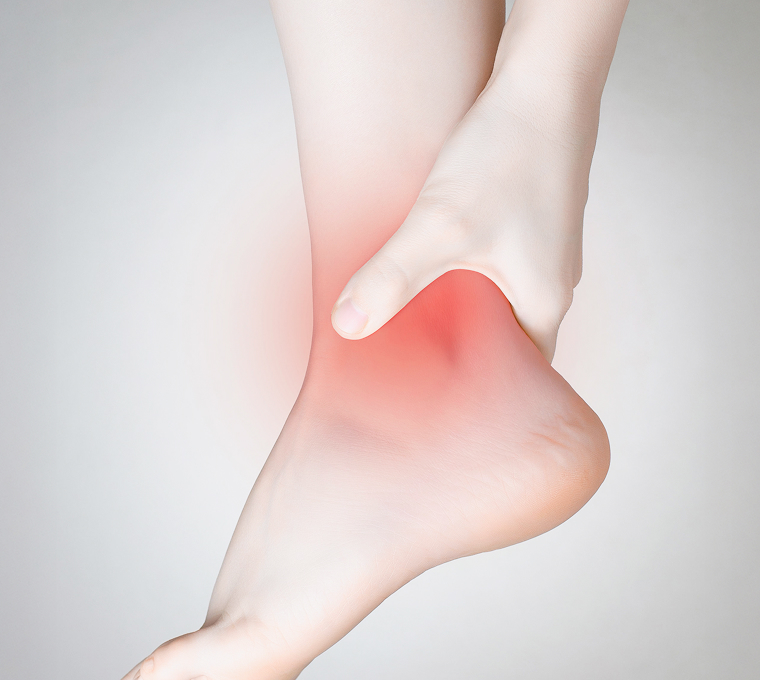

반복되는 목·허리 통증

방치하지 말고 바로 잡으세요!

목 · 허리 통증, 디스크 손상 원인을 파악해

신경 압박과 염증 관리를 통해 증상 완화를 기대 할 수 있습니다.